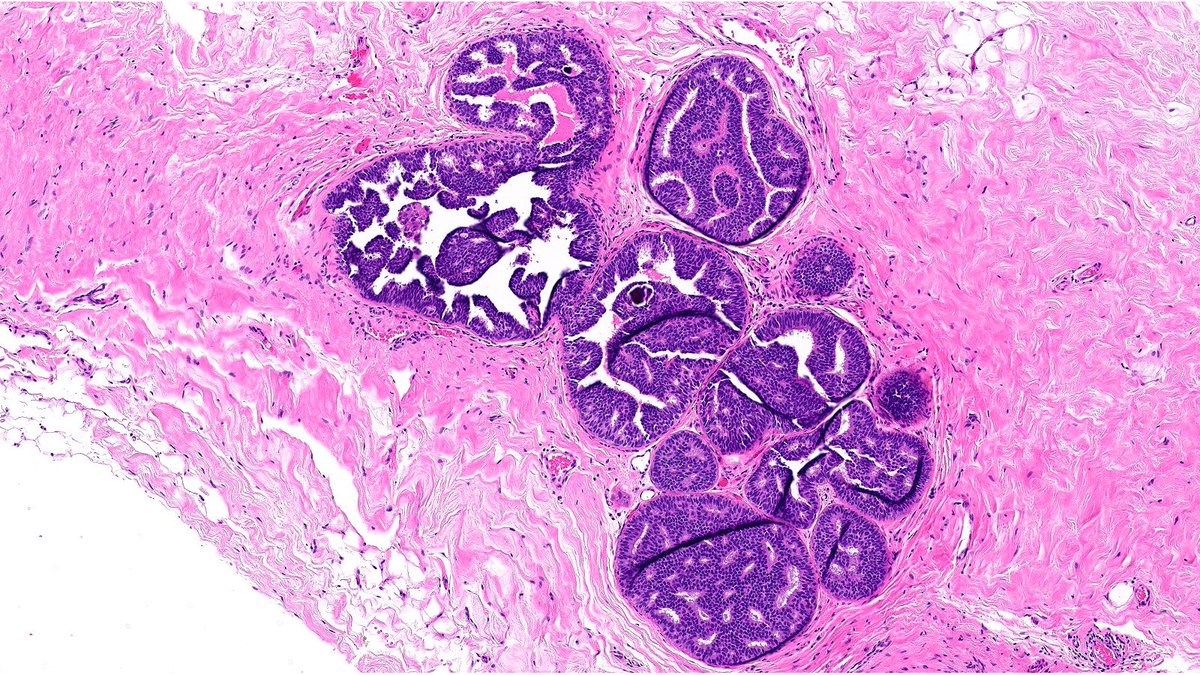

What’s the diagnosis of this papillary breast lesion? 🔬 Cast your vote below 👇 Answer revealed Monday! #PathX #PathTwitter #breastpath #PathQuiz

Delighted to share our latest article, "Challenges in papillary tumors of breast", published with my wonderful colleague @RazaHoda in @Human_Pathology! It's always a joy working together. Check it out here sciencedirect.com/science/articl…